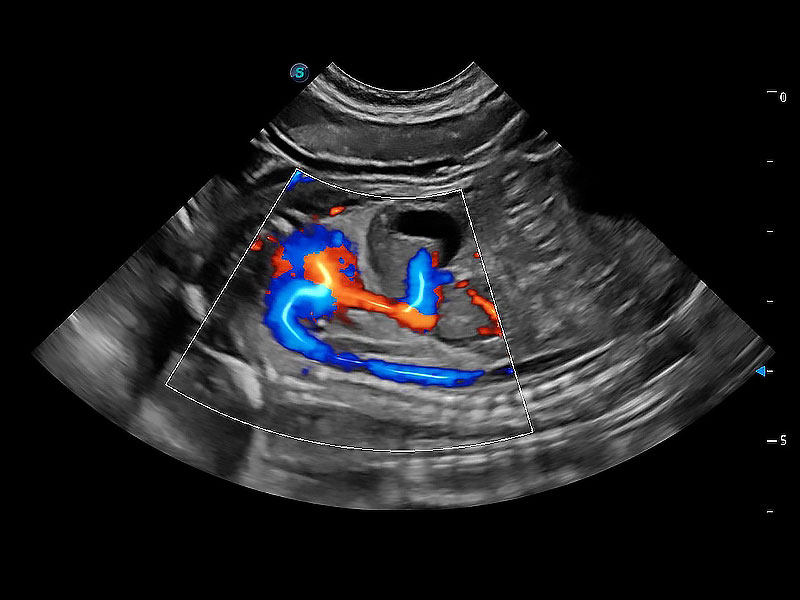

极大提升超低速微细血流的检出能力,同时更精准地滤除软组织和超声信号,为兽用医生提供以往无法通过常规血流获得的疾病诊断信息。